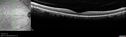

Vision in the right eye is 20/16

Normal Eye - Vision 20/16389 views61 year old female with multiple problems including chronic CME in the left eye.00000